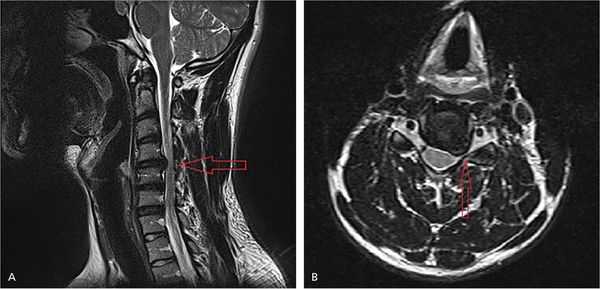

Для уточнения локализации повреждения нервного корешка проводятся нейровизуализационные методы диагностики. Самым информативным является магнитно-резонансная томография (МРТ). Метод позволяет выяснить причину радикулопатии: с его помощью можно увидеть сам нервный корешок и структуры, которые его окружают.

На рисунке А (вид сбоку) стрелкой указана локализация грыжи межпозвонкового диска на уровне шейных С4-С5 позвонков. Грыжа выступает в позвоночный канал и смещает или сдавливает спинной мозг. На рисунке В (вид сверху) стрелкой отмечена та же грыжа, которая выступает влево и сдавливает нервный корешок.